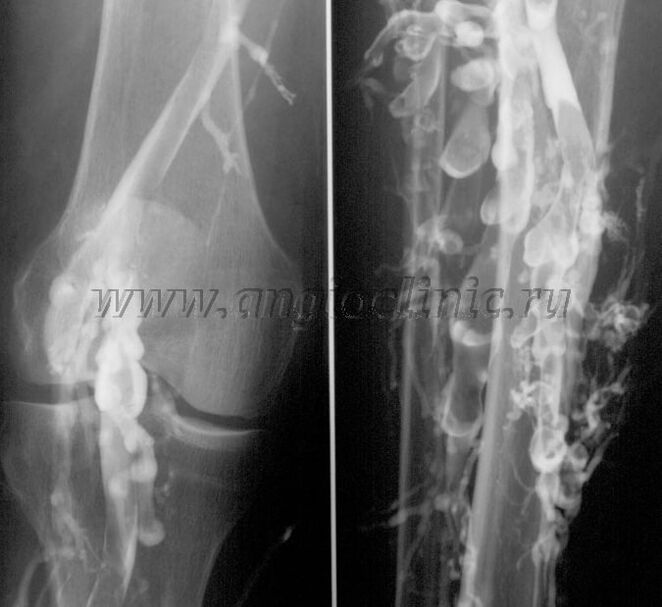

Venografía de contraste

Habitualmente, una ecografía es suficiente para un diagnóstico completo de patología venosa, pero en algunos casos es necesario estudiar la relación entre el estado de los sistemas venosos profundo y superficial, especialmente en casos de varices recurrentes y varices secundarias.

Para resolver este problema, se utiliza un examen de rayos X con contraste. Se punciona la vena safena y se administra contraste. El movimiento del contraste se observa en el monitor del aparato de rayos X y se realizan todas las pruebas y proyecciones necesarias. Actualmente, la venografía para las venas varicosas se utiliza muy raramente.